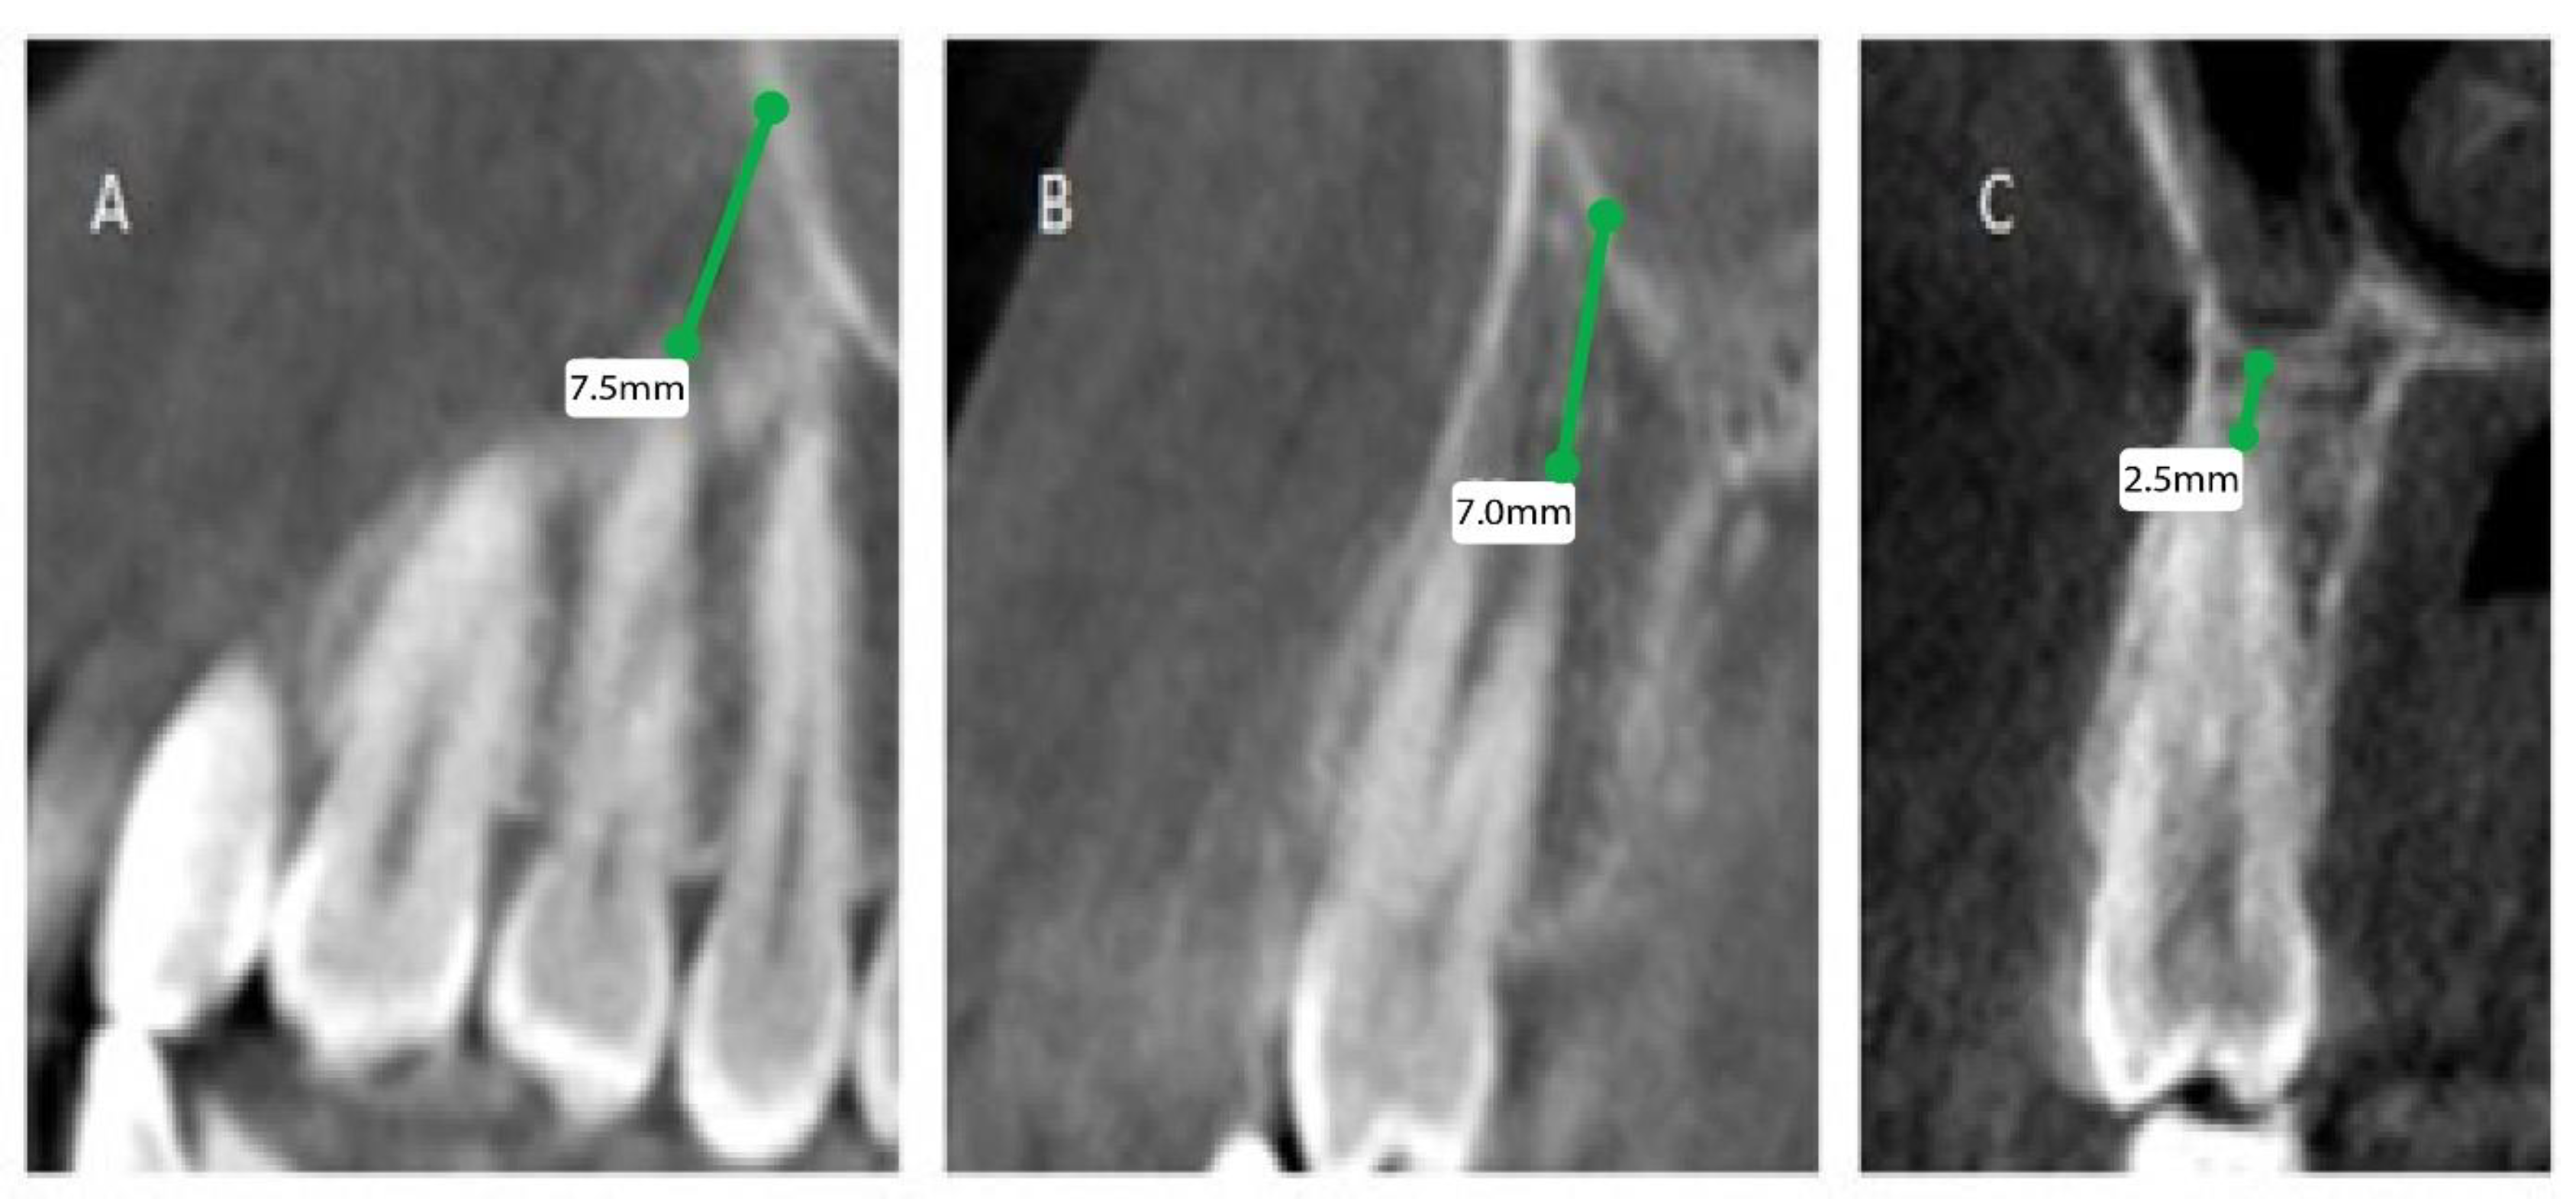

The patients’ files were assessed by the Department of Oral & Maxillofacial Surgery and Diagnostic Sciences, College of Dentistry, Prince Sattam Bin Abdulaziz University, Al-Kharj, Saudi Arabia, to record the gender and the age of the subjects included in the study from September 2020 to December 2020, and further divided as male and female patients, depending on gender and age, into 4 groups (0 to 20, 21 to 40, 41 to 60, and above 60). Mean distances between posterior maxillary roots (PMRs) from different teeth and the maxillary sinus floor (MSF) were measured using a software-calibrated tool. Each measurement was obtained by measuring a line drawn from the MSF to the nearest point of the apex of the root in two views, sagittal and coronal, and the mean distance was calculated (Figure 1, Figure 2 and Figure 3). The distance for each root and each tooth were recorded and transferred to the Excel sheet.

Figure 1.

CBCT sagittal view showing the distance between the maxillary sinus and the root of permanent maxillary (right). (A) First premolar buccal root, (B) first premolar palatal root, (C) second premolar root.